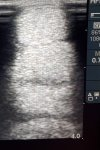

Picture 2 end of March 2020, three months later. The hole had closed up indicating that the tendon fibres have realigned and are healing well. Horse started going out beginning of April in very small paddock which was made bigger over the course of 4 weeks.